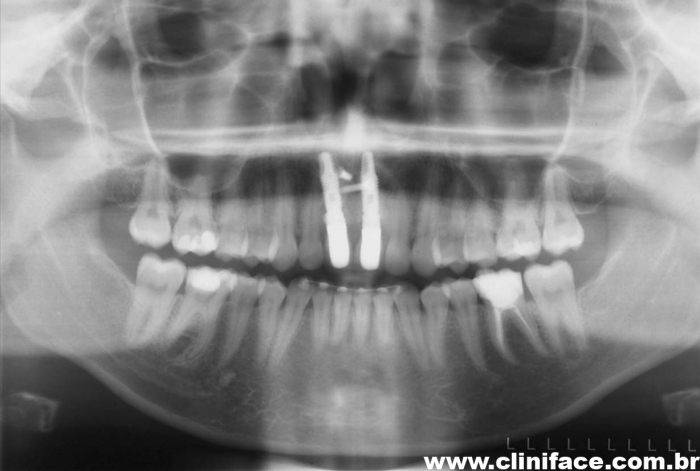

Rx após extração e implantes imediatos